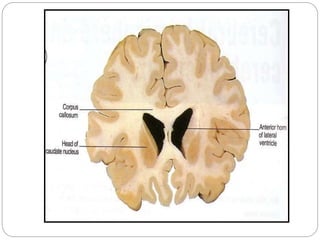

Anterior Horn

 In the frontal lobe.

 Roof:

 Corpus callosum

(trunk)

 Floor:

(Rostrum)

 Caudate nucleus

head

 Anterior:

(Genu)

 Medially:

 Septum pellucidum.